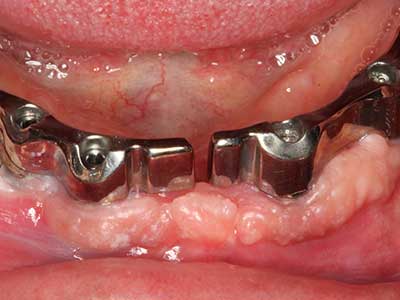

Initial and surgical treatment phases are differentiated in the treatment of marginal periodontitis. In addition to instruction in oral hygiene and motivating patients, both phases should include adequate cleaning of the root surface. In the regenerative setting an open access is generally preferred. The root surface can be cleaned by piezosurgery using special attachments, where instruments with different curvatures are used to reach areas that are difficult to access, such as furcations. The integrated irrigation in the system flushes the detached concrements and bacteria out of the pocket. Specialized systems such as the Piezomed also include application feedback to minimize the ablation of hard dental substance. The greater the pressure on the periodontal attachment the greater the reduction in the amount of ablation.